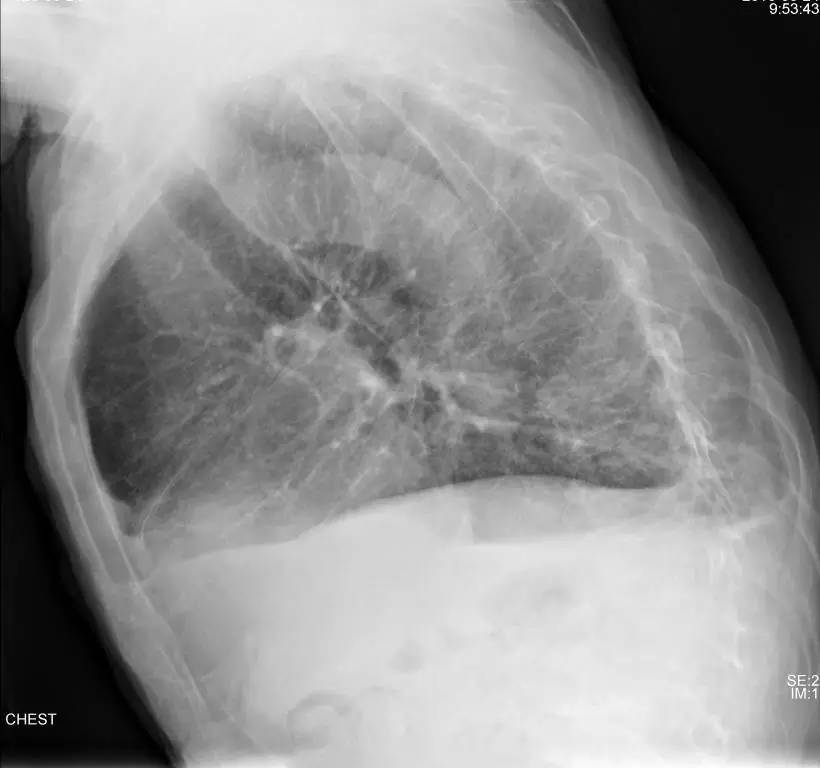

>>>>病例2:男,88y,右侧胸痛月余。

左下肺最有可能的诊断是?

A.包裹性积液

B.胸膜增厚

C.胸腔积液

D.心包脂肪垫